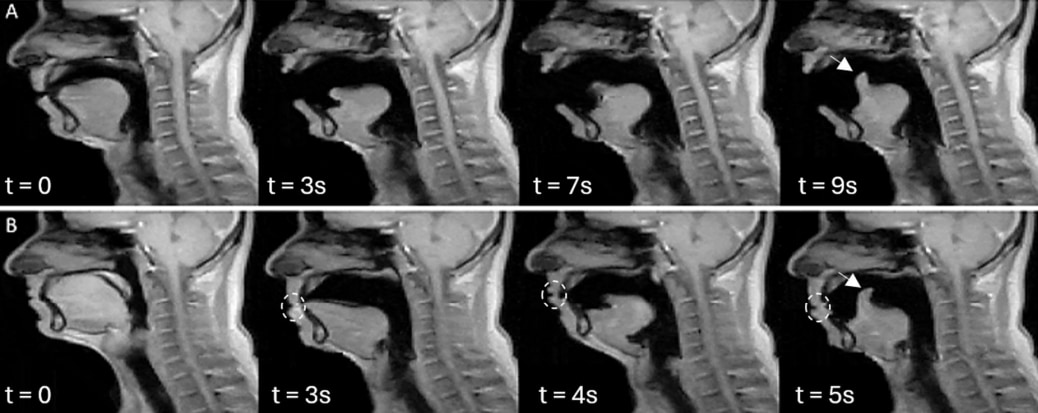

研究ではMRIを使用して、あくびの様子を詳細に記録し分析した - ナゾロジー